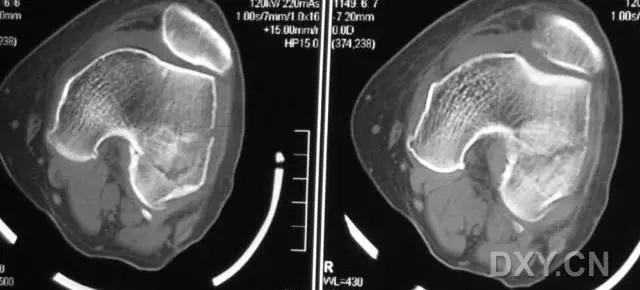

5. Hoffa 骨折

指股骨远端冠状面的骨折。

病例 1:一般股骨髁间、髁上粉碎骨折中含 Hoffa 骨折的不少见,但单纯后髁骨折则很少见。

正位片

侧位片

水平位 CT

第 2 例

第 3 例